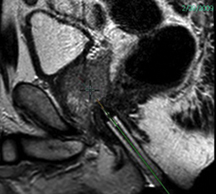

Generally, there are two types of spots on a bone scan. Hot spots form when the radioactive material, or tracer, accumulates in areas of the bone. Cold spots form in areas where the tracer has not accumulated. Bone loss may cause cold spots, while arthritis, infections or broken bones can cause hot spots. Tumors and cancer can cause either type.

Some cancers, such as prostate, lung, and breast cancer, cause hot spots on a bone scan when the cancer has metastasized, or spread to the bone. Bone cancers will also appear as hot spots. These dark areas are due to the growth of excess tissue and the accumulation of the tracer.

Cold spots on a bone scan indicate that the tracer has not accumulated in that section of the bone. A loss of blood flow to the bone, or a bone infarction, can cause this type of spot. When a person suffers a bone infarction, the part of the bone that no longer receives blood can die, leading it to collapse.